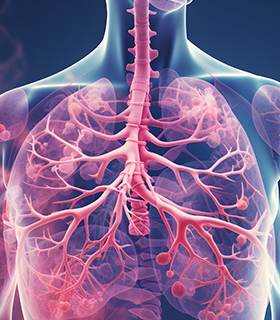

Pulmonary Thromboendarterectomy

Surgery to remove chronic blood clots from the pulmonary arteries, improving lung function and oxygenation.